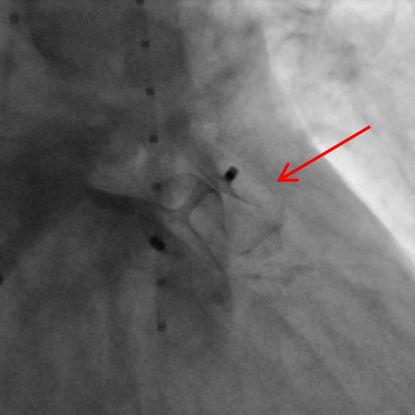

Bild 1a - Pfeil: Darstellung des Vorhofohres mit Kontrastmittel.